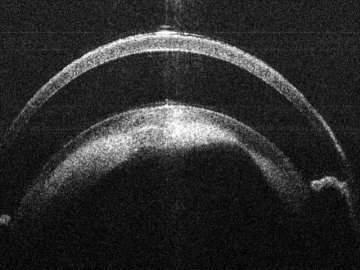

Subretinal Injection

Bioptigen sdOCT anterior Subretinal Injection.